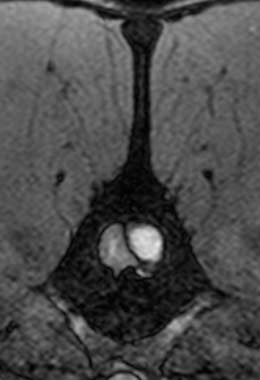

Disc cysts or hydrated nucleus pulposus extrusions (HNPE) are a final form of disc disease that are very similar to Type-I disc disease. The major difference here is that no degeneration of the semi-liquid centre (i.e. the nucleus pulposus) of the disc occurs and so this material leaks out of the ligament (annulus fibrosus) and compresses the spinal cord.

By examining an animal alone, it is impossible to determine how much of each component contributes to the signs. A myelogram, CT scan, or MRI can be used to determine the extent of spinal cord compression. The amount of bruising can, however, be extremely difficult to assess (even with specialised techniques). This concussion can sometimes be seen as spinal cord swelling.

Standard X-rays are rarely enough to diagnose a slipped disc. In a standard X-ray, only the bones of the vertebrae are visible, not the discs between them or the spinal cord. Conventional X-rays can sometimes reveal disc degeneration without the animal showing any symptoms. Only myelography (X-rays taken after injection of dye around the spinal cord), CT (computed tomography) or MRI (magnetic resonance imaging) can reliably diagnose a slipped disc. Tests such as these help to determine whether there is a slipped disc, where it is located, and if there are any other causes of spinal pain or paralysis.